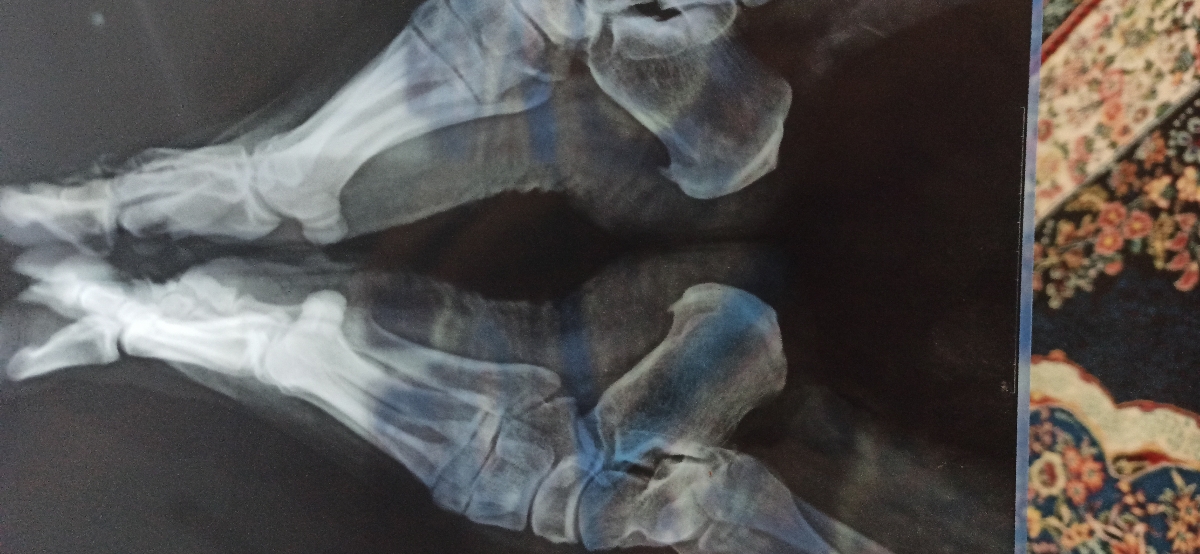

عکس رادیولوژی پاشنه پا

سلام خانم دکتر میشه عکس پای منو ببینید نظر بدید وراه درمان..پاشنه پاهام خیلی دردمیکنه قابل درمان هست

سلام عزیزم خارپاشنه داری ب گمونم

سلام عزیزم اره خودمم حدس میزنم ولی نمیدونم برای درمانش چیکارکنم

خار پاشنه هست مامانم داشت

پدهای سیلیکونی مخصوص خار پاشنه هست از اونا بگیر،بنداز داخل کفشت خیلی خوبه درد پاشنه را کم میکنه ولی باید مدام استفاده کنی.حتی توی خونه یه کتونی سبک بپوش با جوراب پد بنداز داخل کفشت

سلام به روی ماهتون عزیزم

جانم این موارد در حوزه تخصص زنان نیست باید به متخصص مربوطه مراجعه کنید